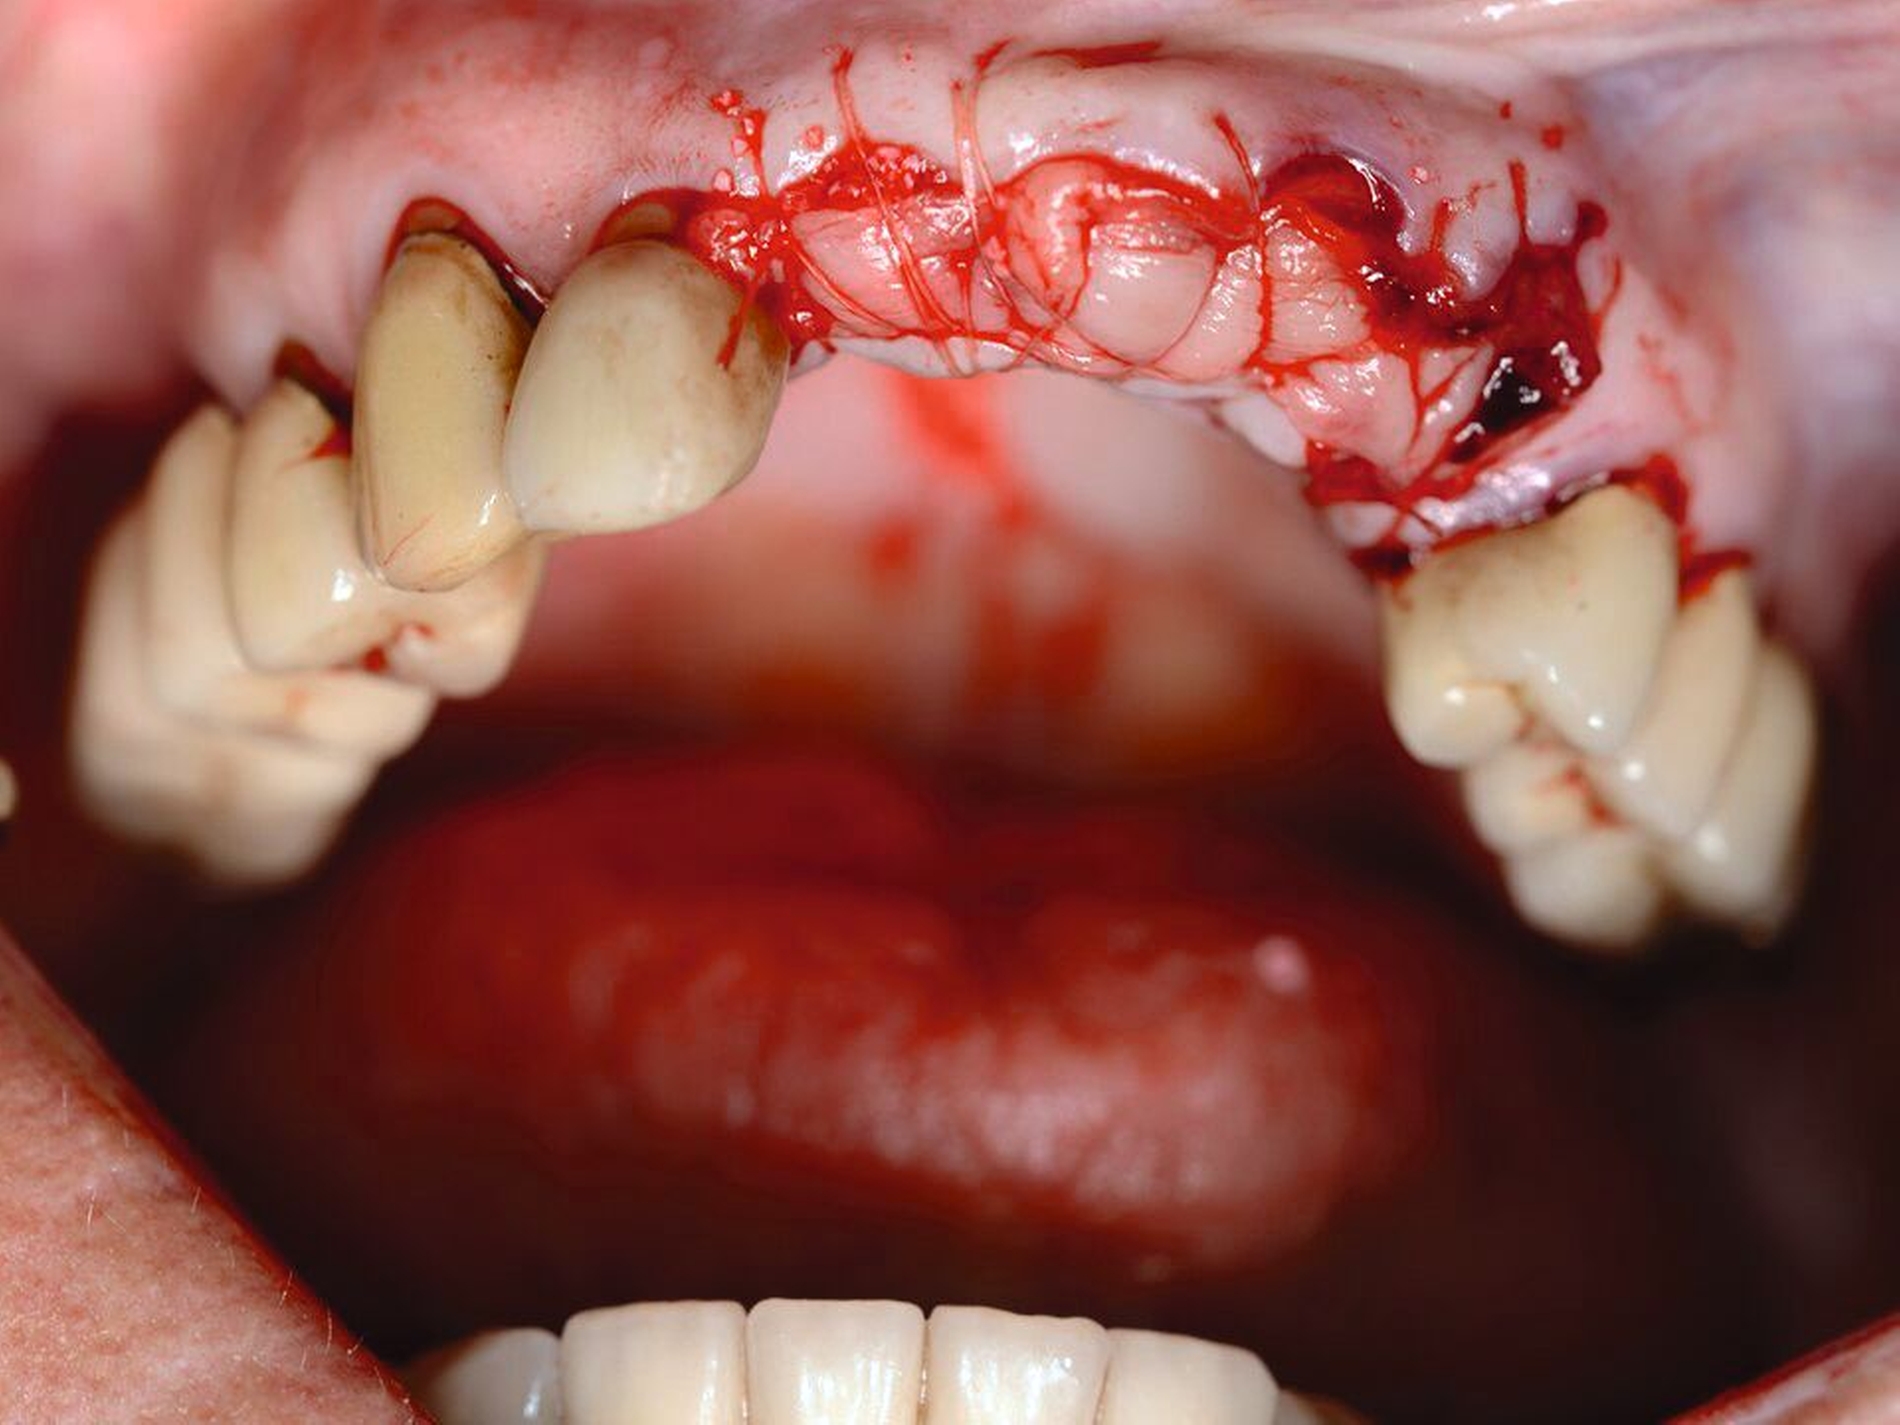

Nach der Einschätzung der Zellvitalität auf der oben genannten Basis folgt die therapeutische Intervention im Sinne der Replantation des betroffenen Zahnes in die gespülte Alveole (vorsichtige Entfernung des Blutkoagulums) mit steriler physiologischer Natriumchloridlösung. Schließlich muss die Replantation schonend erfolgen, da immer mit daran gedacht werden muss, dass es im Rahmen des Traumas zusätzlich zu einer Schädigung des Alveolarknochens gekommen sein kann (Abbildung 1). Diese Schädigung kann eine vollständige oder teilweise Alveolarfortsatzfraktur sein, die entsprechende Beachtung finden sollte. Im Anschluss erfolgt die Schienung des betroffenen Zahnes an den Nachbarzähnen. Dabei sollte ein Zeitraum von ein bis drei Wochen eingeplant werden (Tabelle 1).

Die Replantation sollte langsam und mit wenig Druck erfolgen, um eine zusätzliche Schädigung des Wurzelzements zu vermeiden. Anschließend sollte eine flexible Schienung des Zahnes erfolgen (Empfehlung 50) [Kahler et al., 2016].

Klinisch findet sich neben häufigen, meist vertikalen Schleimhauteinrissen gegebenenfalls eine tastbare Stufenbildung (Abbildung 6). Dislozierte Alveolarfortsatzfrakturen gehen in der Regel mit einer Okklusionsstörung einher, die Sensibilität der betroffenen Zähne geht dabei häufig verloren. Die Therapie der Alveolarfortsatzfrakturen weist einige Besonderheiten auf, die in der entsprechenden Empfehlung der Leitlinie aufgeführt sind.